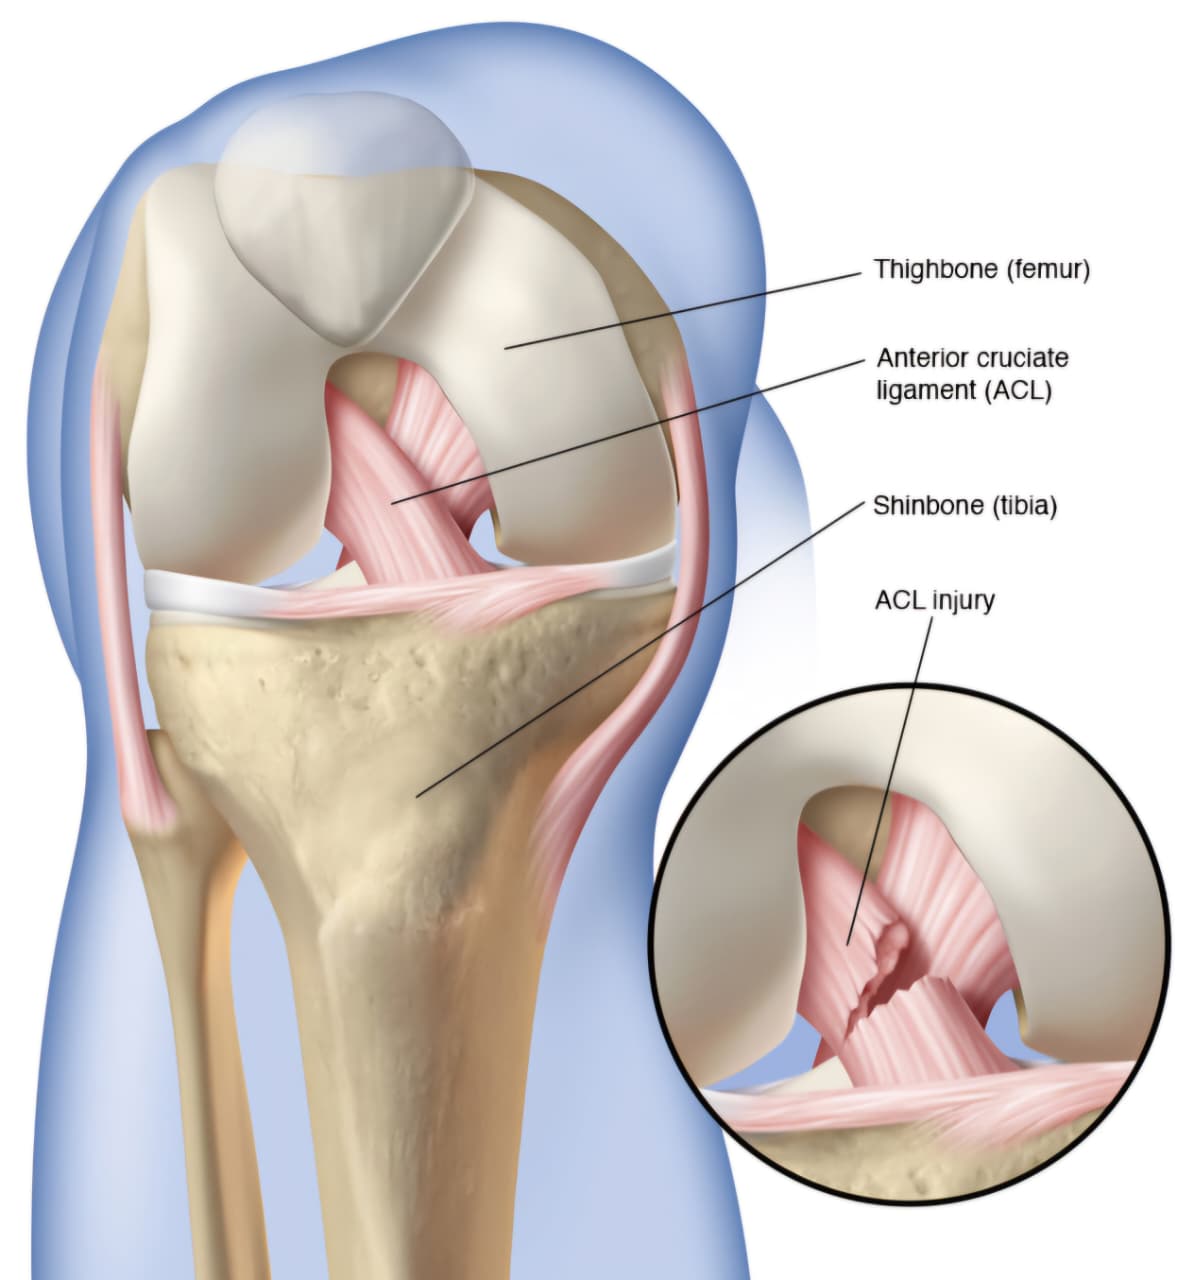

Sports injuries